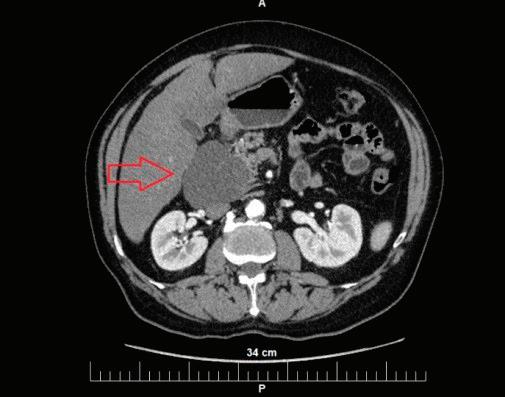

48 КИСТИ НА ПАНКРЕАСАЗНАЧЕНИЕ, ДИАГНОСТИЧНИ ДИЛЕМИ И ИНДИКАЦИИ ЗА ХИРУРГИЯ Н. Шумка, П. Карагьозов

2023 БРОЙ 74 03.2020 СПЕЦИАЛИЗИРАНО ИЗДАНИЕ ЗА ЛЕКАРИ WWW.MEDMAG.BG БРОЙ 74 03.2020 БРОНХОДИЛАТАТОРИТЕ С ДЪЛГО ДЕЙСТВИЕ ПРИ ЛЕЧЕНИЕ НА СТАБИЛНА ХОББ СТР. 4 ХРОНИЧЕН РИНОСИНУИТ С НАЗАЛНА ПОЛИПОЗА И ЕОЗИНОФИЛНО ВЪЗПАЛЕНИЕ СТР. 24 КИСТИЧНИ ПАНКРЕАСНИ НЕОПЛАЗМИ СТР. 62

КИСТИ НА ПАНКРЕАСАЗНАЧЕНИЕ, ДИАГНОСТИЧНИ ДИЛЕМИ И ИНДИКАЦИИ ЗА ХИРУРГИЯ

СТР. 48